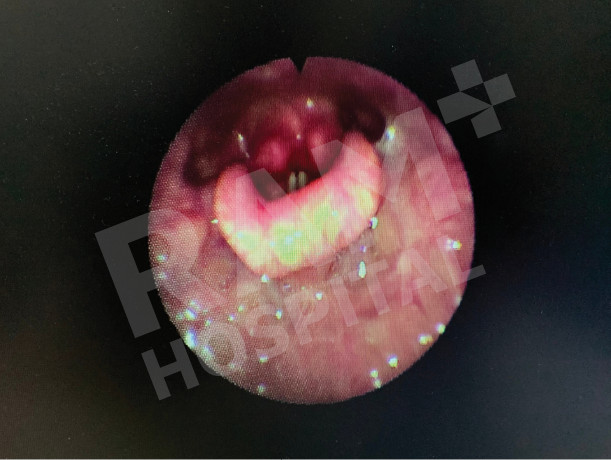

术前

真实案例

术后

Source: Photo courtesy of Dr. Puripan Aramawattanapong, Ear, Nose, and Throat Specialist